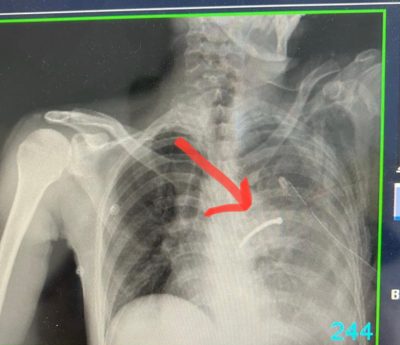

120 دقيقة جراحية تنقذ صدر مقيم اخترقه مسمار بمستشفى الامير مشاري ببلجرشي

تمكن بفضل الله أطباء الباحة المختصين بجراحة فتح الصدر بقيادة استشاري جراحات الصدر د. حسن عثمان الزندي والطاقم الطبي من جراحين د. علي ناجي ود. ناصر عسيري وطاقم التخدير وتمريض وتعقيم في مستشفى الأمير مشاري بن سعود من إنقاذ حياة مقيم باكستاني الجنسية تعرض لإصابة عمل خطيرة جراء استخدامه مسدس المسمار اثناء تاديته العمل والذي تسبب للمصاب باختراق الصدر وإصابة الرئة وأحد الشرايين الرئوية وأدى إلى نزيف حاد في الصدر وتجمع هوائي .

وأكدت صحة الباحة ان المصاب احضر إلى قسم الطوارئ وهو في حالة حرجة جداً حيث كان يعاني إنخفاض الضغط ونزف لأكثر من ثلاثة لتر من الدم وعلى الفور وبعد إجراء الفحوصات السريرية والأشعة اللازمة تقرر إدخاله غرفة العمليات كحالة إنقاذ حياة وقام الأطباء بعمل عملية استغرقت أكثر من ساعتين لفتح الصدر وإيقاف النزيف وإستئصال أحد فصوص الرئة اليسرى وإستخراج المسمار وتعويض الدم المفقود .

وأشارت أنه تم نقل المريض بعد إستقرار الحالة إلى غرفة العناية المركزة لمدة أسبوع ثم نقله إلى قسم التنويم وبعدها غادر المستشفى بصحة جيدة ولله الحمد .

وبينت صحة الباحة أن هذه الإصابة تعد من الإصابات الخطيرة التي قد تؤدي إلى الوفاة بنسبة كبيرة 100% لاقدر الله .